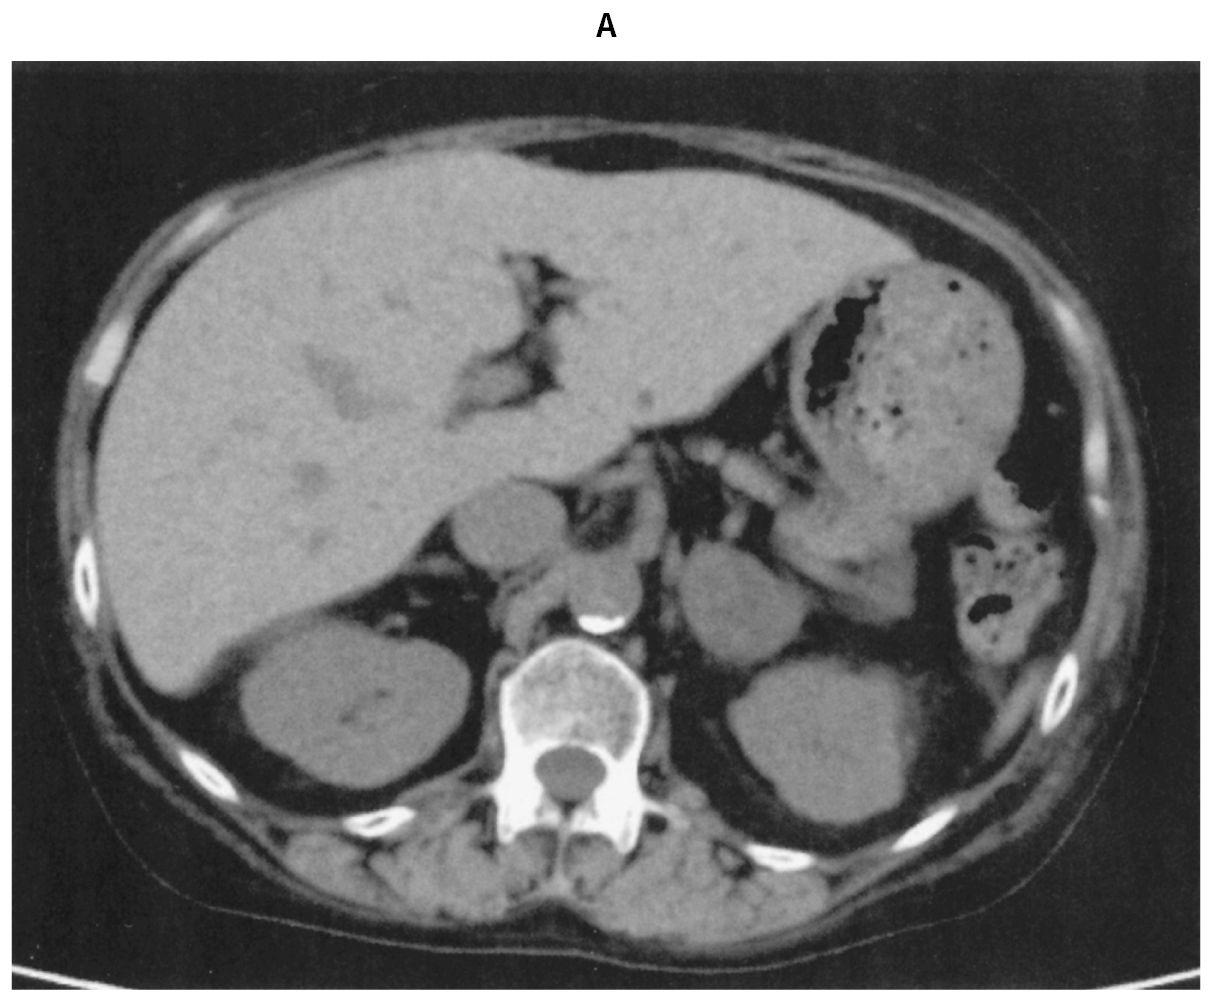

48歳の女性。人間ドックで副腎腫瘤を指摘され来院した。数年前から高血圧症に対してカルシウム拮抗薬とアンジオテンシンⅡ受容体拮抗薬を内服中である。身長160cm,体重66kg。脈拍72/分,整。血圧130/84mmHg。満月様顔貌および水牛様肩がみられる。血液生化学所見:空腹時血糖110mg/dL,HbA1c 6.2%(基準4.9~6.0),トリグリセリド154mg/dL,LDLコレステロール182mg/dL,Na 142mEq/L,K 3.8mEq/L,Cl 104 mEq/L,血漿レニン活性1.6ng/mL/時間(基準1.2~2.5),アルドステロン48pg/mL(基準4~82),ACTH 1.4pg/mL(基準60以下),コルチゾール24.2μg/dL(基準5.2~12.6),アドレナリン8pg/mL(基準100以下),ノルアドレナリン124pg/mL(基準100~450)。少量デキサメタゾン(1mg)抑制試験は陽性であった。腹部単純CT(A)と副腎皮質シンチグラム(B)を下に示す。治療として副腎腫瘤の摘出手術を予定している。